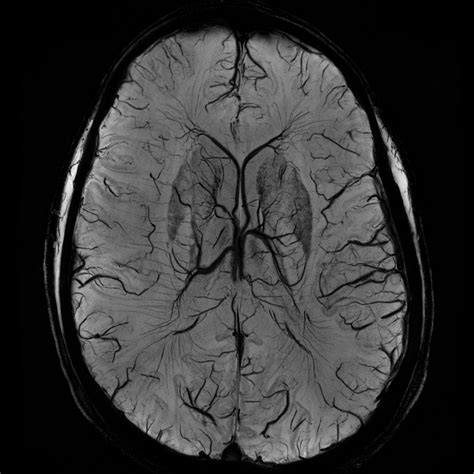

By highlighting these specific areas, the contrast agent allows radiologists to distinguish healthy tissue from diseased tissue. It acts like a spotlight, making lesions, tumors, or areas of inflammation "light up" on the resulting images. Without this enhancement, subtle abnormalities might remain hidden, leading to potentially delayed or incorrect diagnoses.

After your brain MRI with contrast is completed, the images are sent to a radiologist—a doctor specialized in interpreting medical scans. They examine the images, comparing the non-contrast and contrast-enhanced sets to identify any anomalies. This analysis is compiled into a formal report, which is then sent to your referring physician. Your doctor will then discuss these results with you, explaining what was found and determining the next steps in your care plan. It is common to feel anxious while waiting for results; however, remember that these scans are intended to provide clarity and guide the most effective treatment path for your unique situation.

• mri brain with contrast images